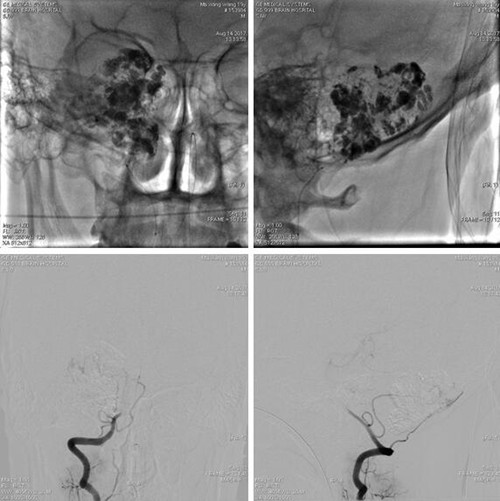

用微导管经右侧椎动脉V3段分支向肿瘤首先注入碘油3ml弥散入肿瘤染色区域,后用10% GLUBRAN2 0.4mL弥散至肿瘤供血微小血管及部分主干,复查造影显示肿瘤栓塞约90%。

2017-8-14介入栓塞后即行肿瘤切除术